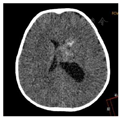

CT检查:左侧脑室体部团块状稍高密度影(图1),CT值约38 HU,大小约32.6 mm(前后径)×28.3 mm(左右径)×29.1 mm(上下径),左侧脑室后角明显扩大。MRI平扫+增强:(1)左侧脑室体部团块状混杂信号,T1WI、T2WI以等高信号为主,其内可见小片状低信号,FLAIR呈等高信号,DWI以高信号为主,增强扫描后肿块中心可见不均匀中等强化,余颅内未见明显异常强化(图2,图3,图4,图5);(2)MRS:肿块内测量NAA/Cr降低,Cho/Cr、Cho/NAA明显升高(图6);(3)头颅MRA未见明显异常;脑电图示轻度异常脑电图。影像检查提示高级别恶性肿瘤性病变,首先考虑间变性室管膜瘤,脉络丛乳头状癌及胚胎性肿瘤不除外。

GG在颅内的影像表现具有多样性,是一种少见的颅内原发性肿瘤,好发于大脑半球的浅表部位,多见于颞叶。影像上主要分为囊性、囊实性、实性3种。囊变和钙化被认为是节细胞胶质瘤的常见表现。Majores等[10]认为囊性病变并壁结节钙化是GG的特征性表现之一。本例发生于左侧脑室前角内,较为罕见,病变以软组织密度/信号为主,内见散在斑片状钙化,没有脑室外GG常见的囊变表现。病变局部与左侧脑室前角壁分界欠清,磁共振DWI呈较高信号,提示弥散受限,多考虑高级别肿瘤;结合MRS示NAA/Cr降低,Cho/Cr明显升高,术前影像首先考虑间变性室管膜瘤,其次考虑脉络丛乳头状癌。幕上室管膜瘤/间变性室管膜瘤分属WHO Ⅱ~Ⅲ级,幕上可位于侧脑室、脑实质或骑跨生长[11],肿瘤内可出现钙化、囊变和出血,密度或信号较为混杂,DWI提示弥散受限时,多考虑间变性室管膜瘤。本例未见明显囊变和出血成分,增强后未呈现室管膜瘤典型的环形强化[12],与室管膜瘤/间变性室管膜瘤不太符合。脉络丛乳头状瘤好发于脑室,尤其是侧脑室内,WHO分Ⅰ~Ⅲ级,Ⅲ级脉络丛乳头状癌具有高级别恶性肿瘤特征性表现:DWI弥散受限、合并出血、钙化、囊变,可突破侧脑室壁侵犯邻近脑实质,也可随脑脊液播散转移[13],因常起源于脉络丛,可分泌脑脊液,示侧脑室扩大,与本例较为相似。不过结合冠状位观察本例病变部分阻塞侧脑室侧孔可能是导致左侧脑室积水主要原因;因肿瘤生长挤压侧脑室壁变形扩大且分界不清,而并非直接侵犯侧脑室壁。此表现影像鉴别尤为重要,本例肿瘤DWI呈现较高信号,提示弥散受限,且MRS提示Cho/Cr明显升高,易与侧脑室好发恶性肿瘤混淆。术后回顾分析图像本例以实性为主伴少量钙化,不伴水肿及周围组织侵犯,发生于孟氏孔附近,符合节细胞胶质瘤良性表现,但考虑到弥散受限以及MRS中Cho/Cr明显升高,笔者认为不除外肿瘤向更高级别演变可能,这需结合临床长期随访,总结经验。